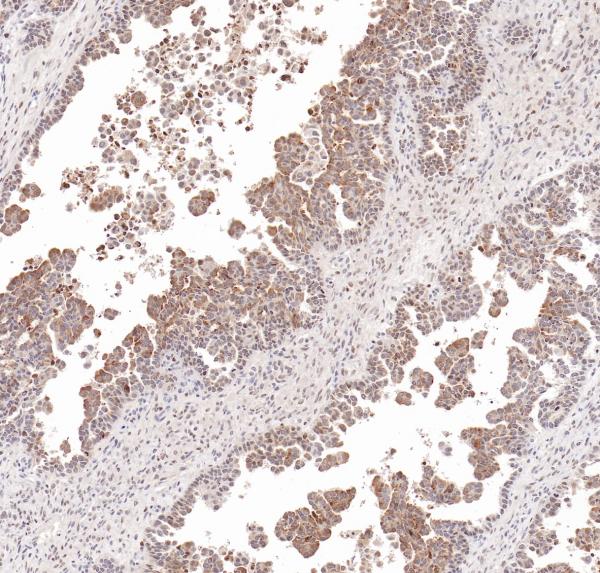

HER2

BP6020